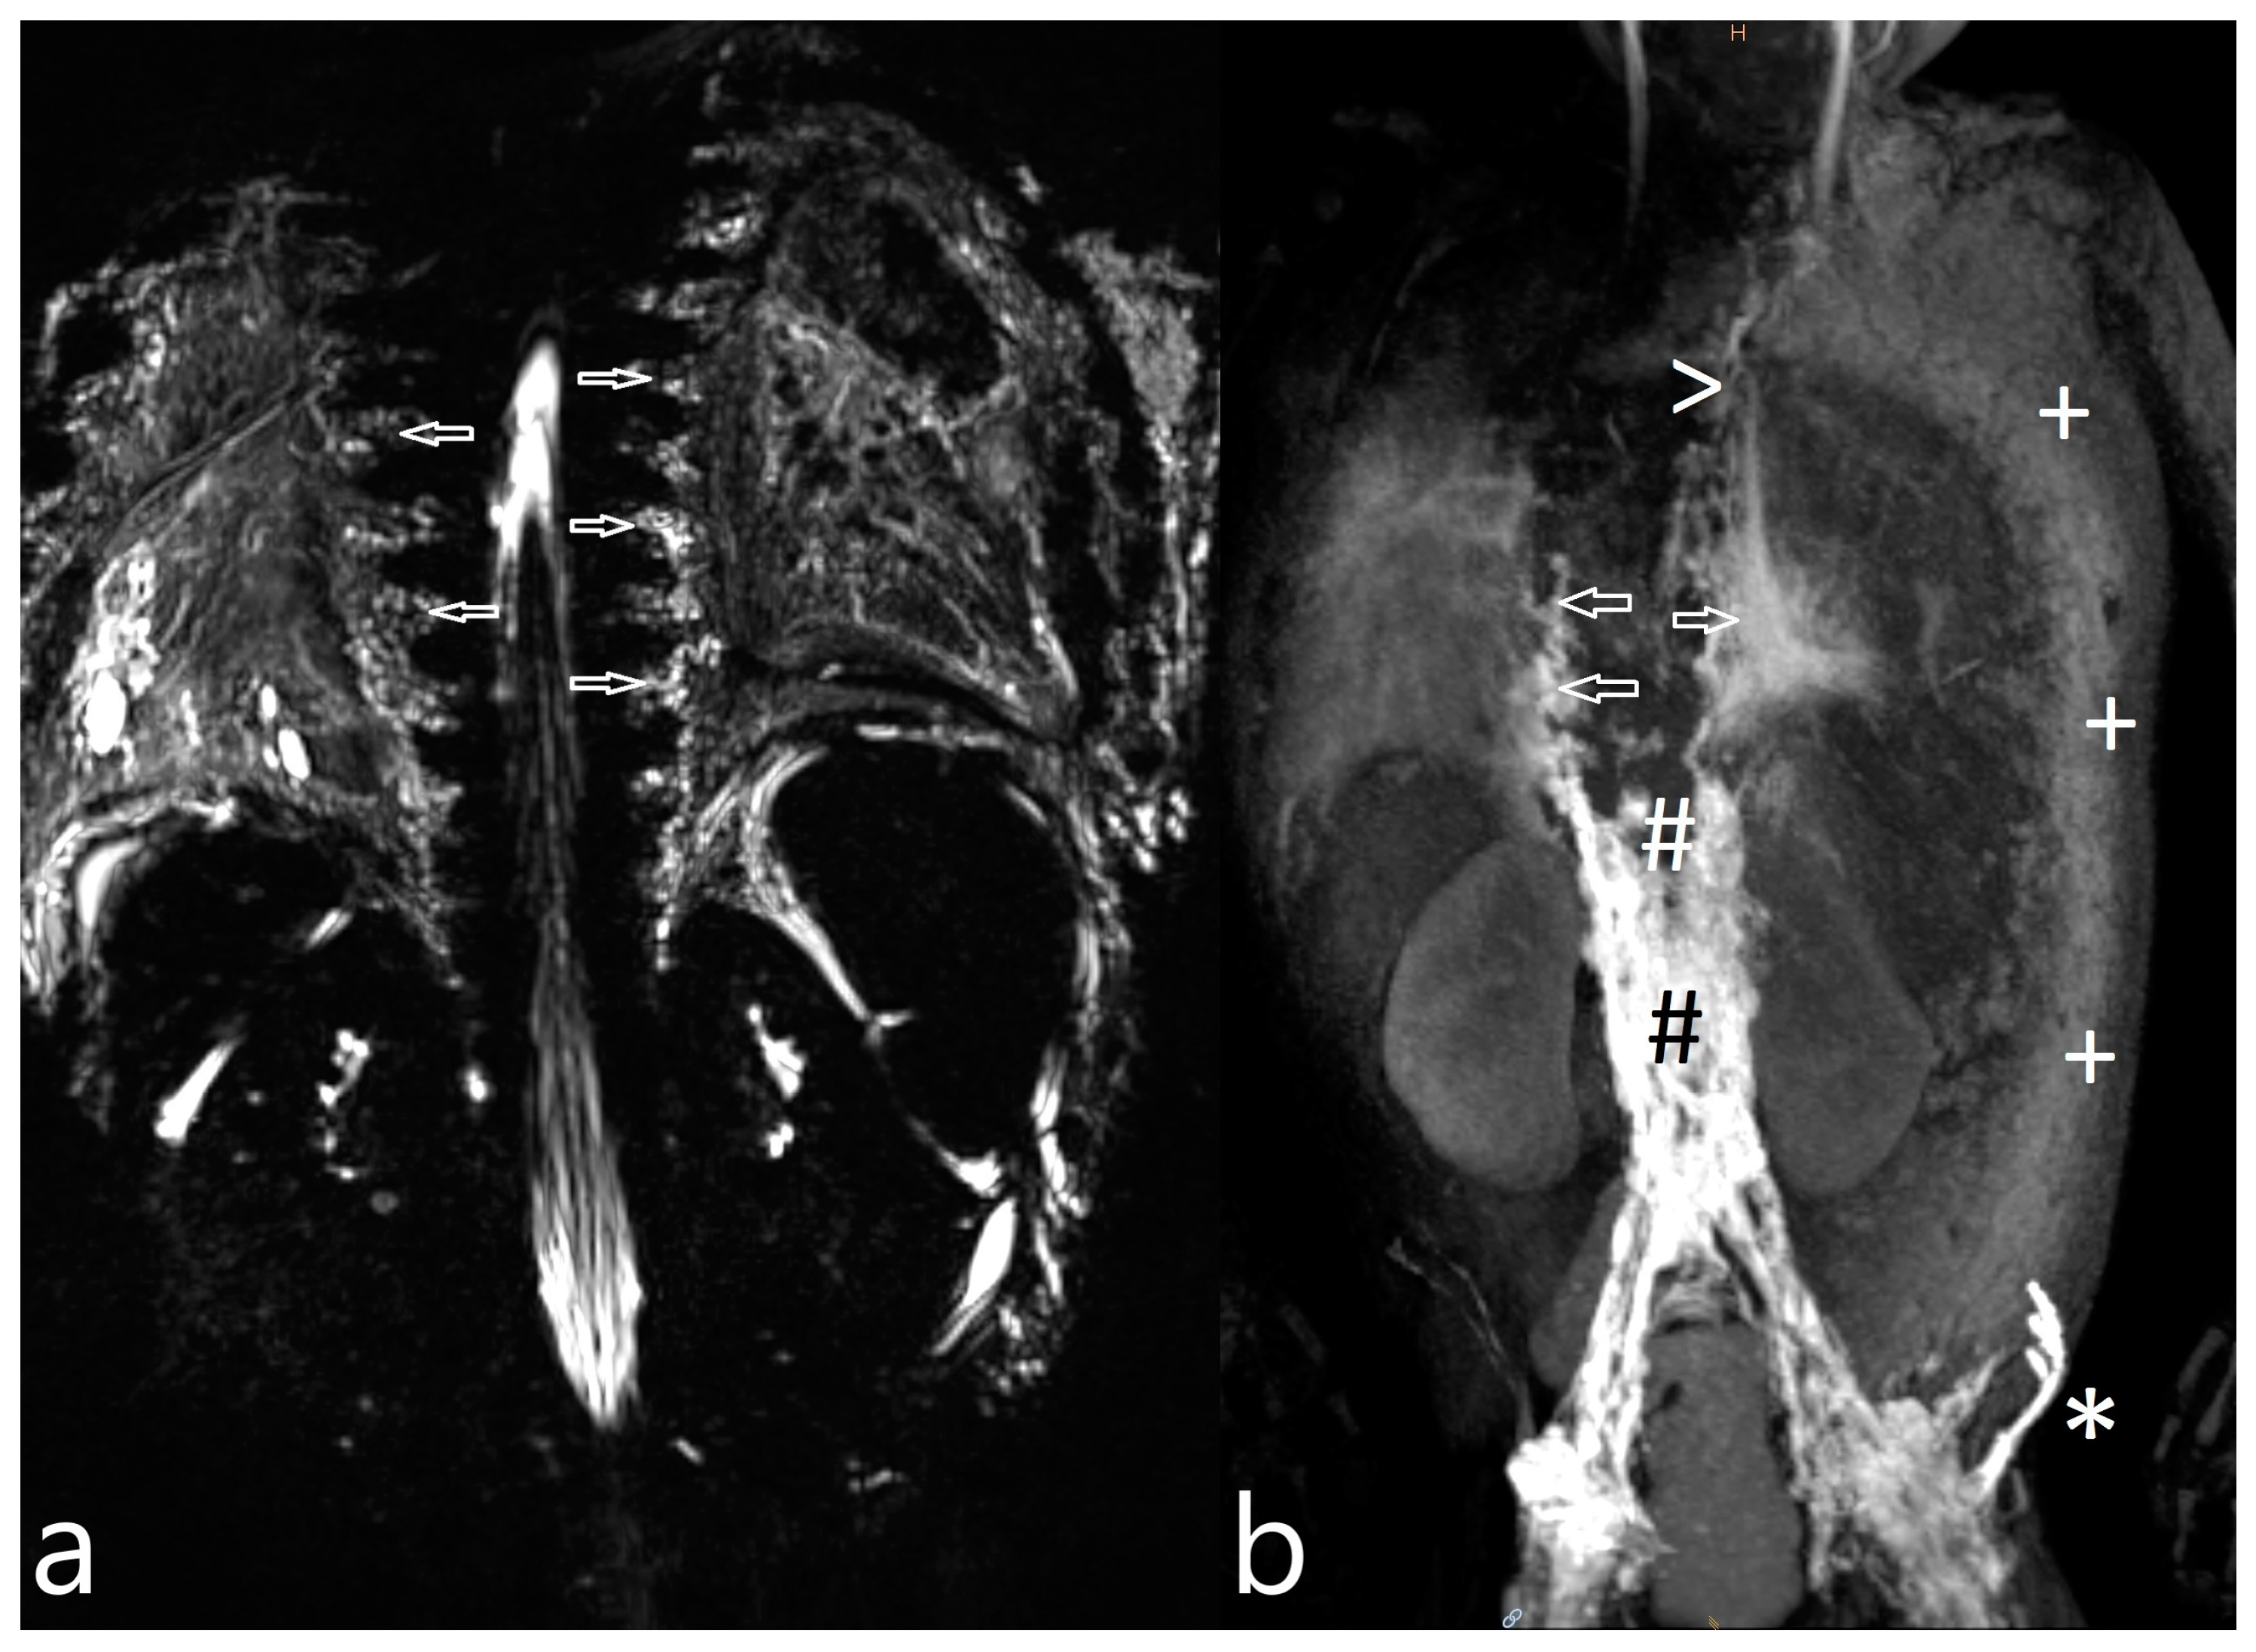

| 4 | 1 | increased signal neck le | TD intact, reduced flow, retrograde flow towards pleural space le | T | no fistula visualized | MCT diet, octreotide | revision | resolution (57/73/82/8) |

| 5 | 4 | increased signal neck, axilla, mediastinum, hilum and body wall, pleural effusion le > ri, ascites | TD intact, retrograde flow towards hilum le, dermal backflow in abdominal wall, reduced central flow | CLFD | no fistula visualized | CT revision, furosemide, etacrynic acid, captopril, | MCT diet | resolution (21/44/63) |

| 6 | 4 | increased signal neck, axilla, mediastinum, hilum and body wall, pleural effusion, ascites | TD intact, delayed central lymphatic flow, retrograde flow towards pleural space ri > le, hilum le, dermal backflow in thoracic and abdominal wall | CLFD | no fistula visualized | CT revision | not indicated | died (20/-/-) |

| 7 | 4 | increased signal neck, mediastinum and hilum, bilateral pleural effusion | TD intact, retrograde flow towards mediastinum and lung parenchyma bilateral | PLPS | TD bilateral TV 2 | CT revision, levosimedane | MCT diet, sandostatin, levosimedane | resolution (31/63/75)) |

| 8 | 3 | increased signal neck, axilla le > ri, mediastinum le > ri, pleural effusion | TD intact, retrograde flow to mediastinum, lung ri | PLPS | no fistula visualized | MCT diet | revision | resolution (22/42/50/19) |

| 9 | 4 | increased signal neck, axilla, mediastinum, hilum and body wall, pleural effusion ri > le, ascites | TD discontinued from LV 3 | CLFD | no fistula visualized | CT revision | MCT diet | resolution (24/44/59) |

| 11 | 3 | increased signal neck le > ri, mediastinum and hilum ri > le, pleural effusion | TD intact, retrograde flow towards mediastinum and hilum le | PLPS | no fistula visualized | diet modification | revision | resolution (42/62/71/20) |

| 12 | 4 | increased signal neck le > ri, mediastinum and hilum ri > le, pleural effusion ri > le, ascites | TD intact, retrograde flow towards mediastinum, hilum, lungs ri > le | PLPS | no fistula visualized | MCT diet, somatostatin | Glenn takedown | resolution (84/142/208/37) |

| 13 | 4 | increased signal neck, axilla, mediastinum, hilum and body wall, pleural effusion | retrograde flow towards hilum le, dermal backflow into thoracic wall | CLFD | TV 7–10 to hilum/ mediastinum | MCT diet | not performed yet | recurrent CT |